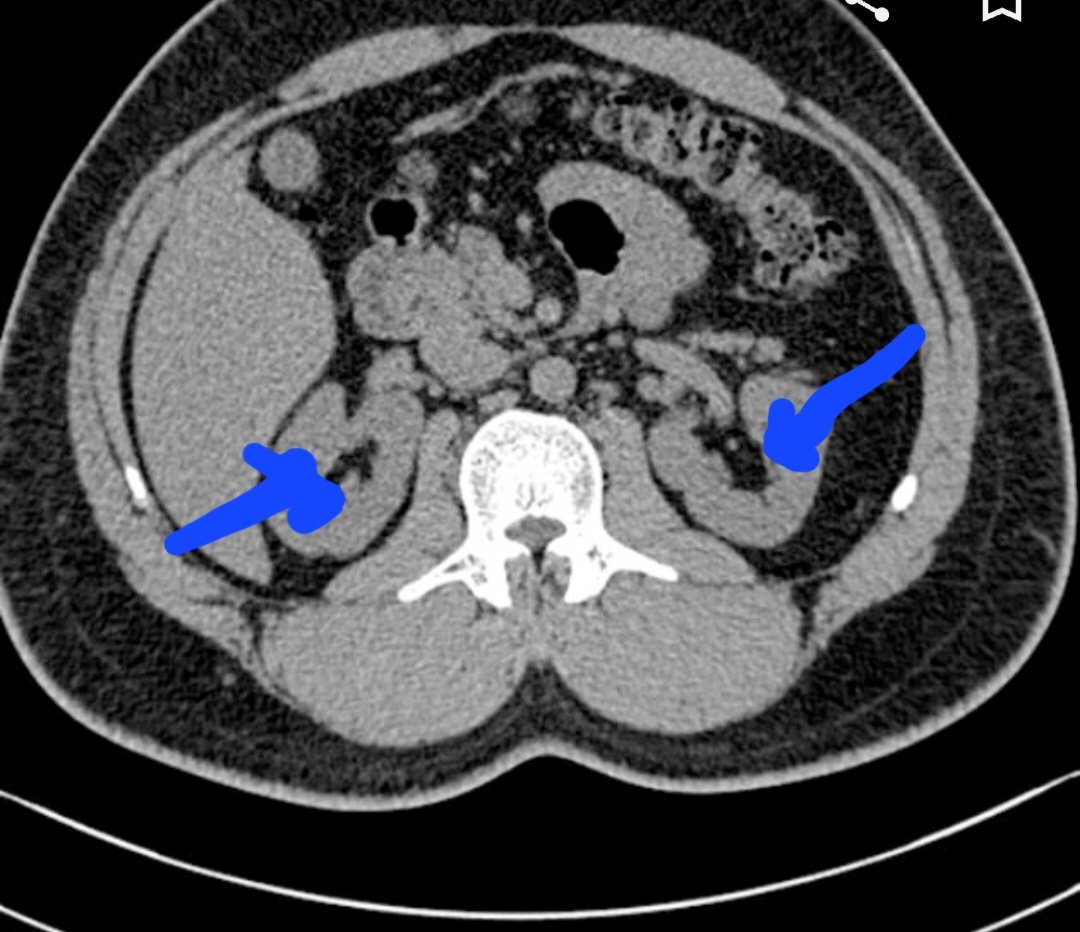

Seperti pd gambar di kiri bawah yg sy lingkari biru adalah ginjal yg bengkak hampir sama kayak kasus ini. (Ini bukan ct scan pasien sy)

Bandingkan dgn gambar kanan. Panah menunjukkan kedua ginjal yg normal (kanan & kiri).